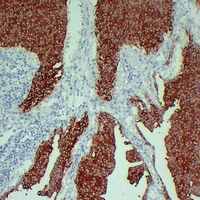

(Immunohistochemical analysis of Cytokeratin 13 staining in human tonsil formalin fixed paraffin embedded tissue section. The section was pre-treated using heat mediated antigen retrieval with sodium citrate buffer (pH 6.0). The section was then incubated with the antibody at room temperature and detected using an HRP conjugated compact polymer system. DAB was used as the chromogen. The section was then counterstained with haematoxylin and mounted with DPX.)

(Immunohistochemical analysis of Cytokeratin 13 staining in human squamous cell lung carcinoma formalin fixed paraffin embedded tissue section. The section was pre-treated using heat mediated antigen retrieval with sodium citrate buffer (pH 6.0). The section was then incubated with the antibody at room temperature and detected using an HRP conjugated compact polymer system. DAB was used as the chromogen. The section was then counterstained with haematoxylin and mounted with DPX.)

(Immunohistochemical analysis of Cytokeratin 13 staining in human transitional cell carcinoma formalin fixed paraffin embedded tissue section. The section was pre-treated using heat mediated antigen retrieval with sodium citrate buffer (pH 6.0). The section was then incubated with the antibody at room temperature and detected using an HRP conjugated compact polymer system. DAB was used as the chromogen. The section was then counterstained with haematoxylin and mounted with DPX.)